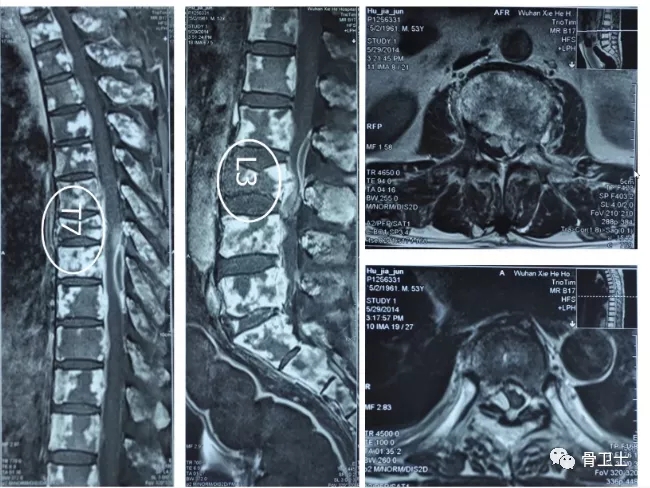

病例三

1619155917449051.jpg

骨巨细胞瘤是一种局部侵袭性肿瘤,来源于骨内成骨的间充质组织,主要由单核基质细胞和多核巨细胞构成。根据组织学特点,可分为三级,Ⅰ级为良性,Ⅱ级为过渡类型,Ⅲ级为恶性。骨巨细胞瘤常见于20-45岁患者。

此病例患者为骨巨细胞瘤患者。在股端和干后端都有影像表现,骨皮质有所破裂。术前给患者做了活体组织检查、CT、核磁等,诊断为骨巨细胞瘤。术中发现皮质破裂比骨肉瘤少一些,比较完整,与骨肉瘤是不同的。关节置换术后患者活动度较好,满意度高。